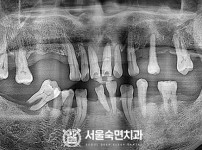

임플란트-전후사진1